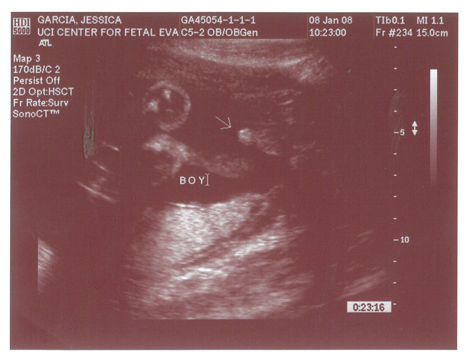

Yes we got a new dsmer coming into the world soon. We got our ultrasound today and its gonna be a boy. And shes a lot further along then we had originally thought. Shes due on April 15th which puts her at almost 6.5 months, (and really not showing it.) He weighs currently ~2lbs. He even opened his mouth while on camera which was really cool.

Here are the pics.

Pic 2: Mouth is open!

Pic 3: NWS Baby Penis! lol